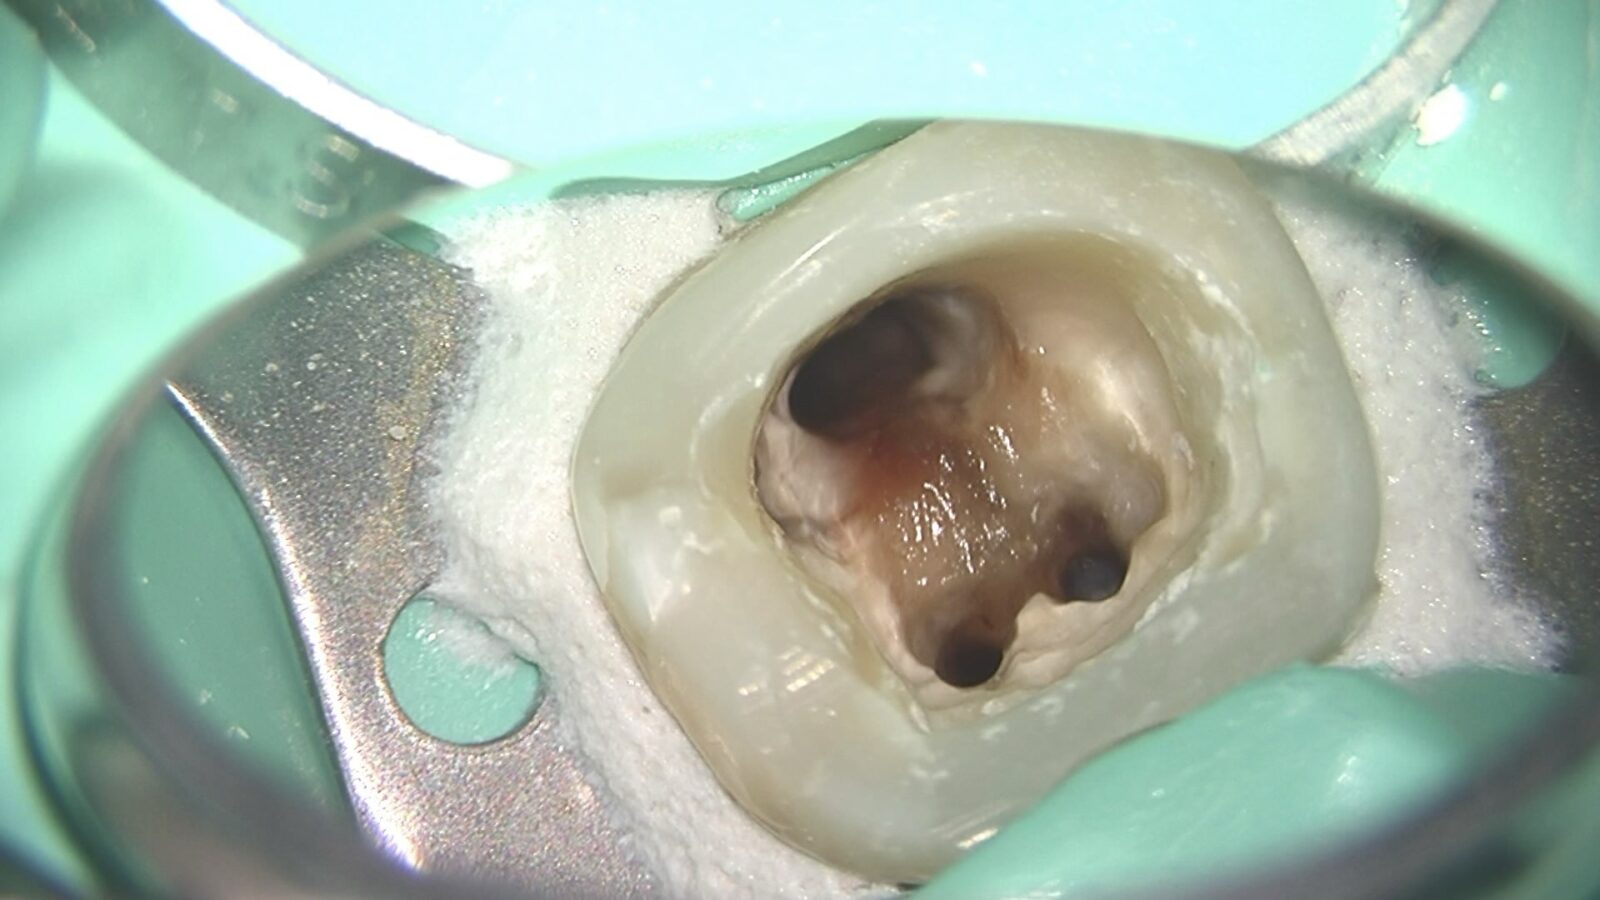

下の画像をご覧ください。黒く見えている部分が、歯の内部にある根管です。

根管はまっすぐではなく、枝分かれや湾曲をしていることが多く、直径が1mmに満たない細い部分もあります。このような構造の中から感染した組織を取り除くには、高い精度が求められます。

当院では、根管内を正確に把握するため、歯科用のマイクロスコープ高倍率ルーペを使用して治療を行っています。

視野を拡大しながら処置を行うことで、感染源の取り残しを防ぎ、治療精度の向上につなげています。

右の画像では、マイクロスコープを通して見た根管内部の様子です。

肉眼では把握できない細部まで確認しながら治療を行っていることがわかります。